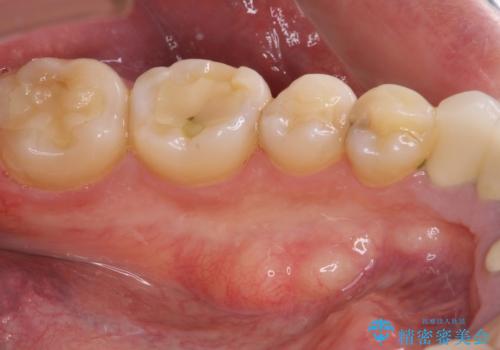

- 張り出している骨隆起による話しにくさを気にして来院された患者様です。

目視でも大きいと分かる骨隆起が認められたため、歯肉を切開した上で切除することとしました。

また、付近の歯に大きなむし歯が認められたため、セラミックインレーによる修復治療も行うこととしました。